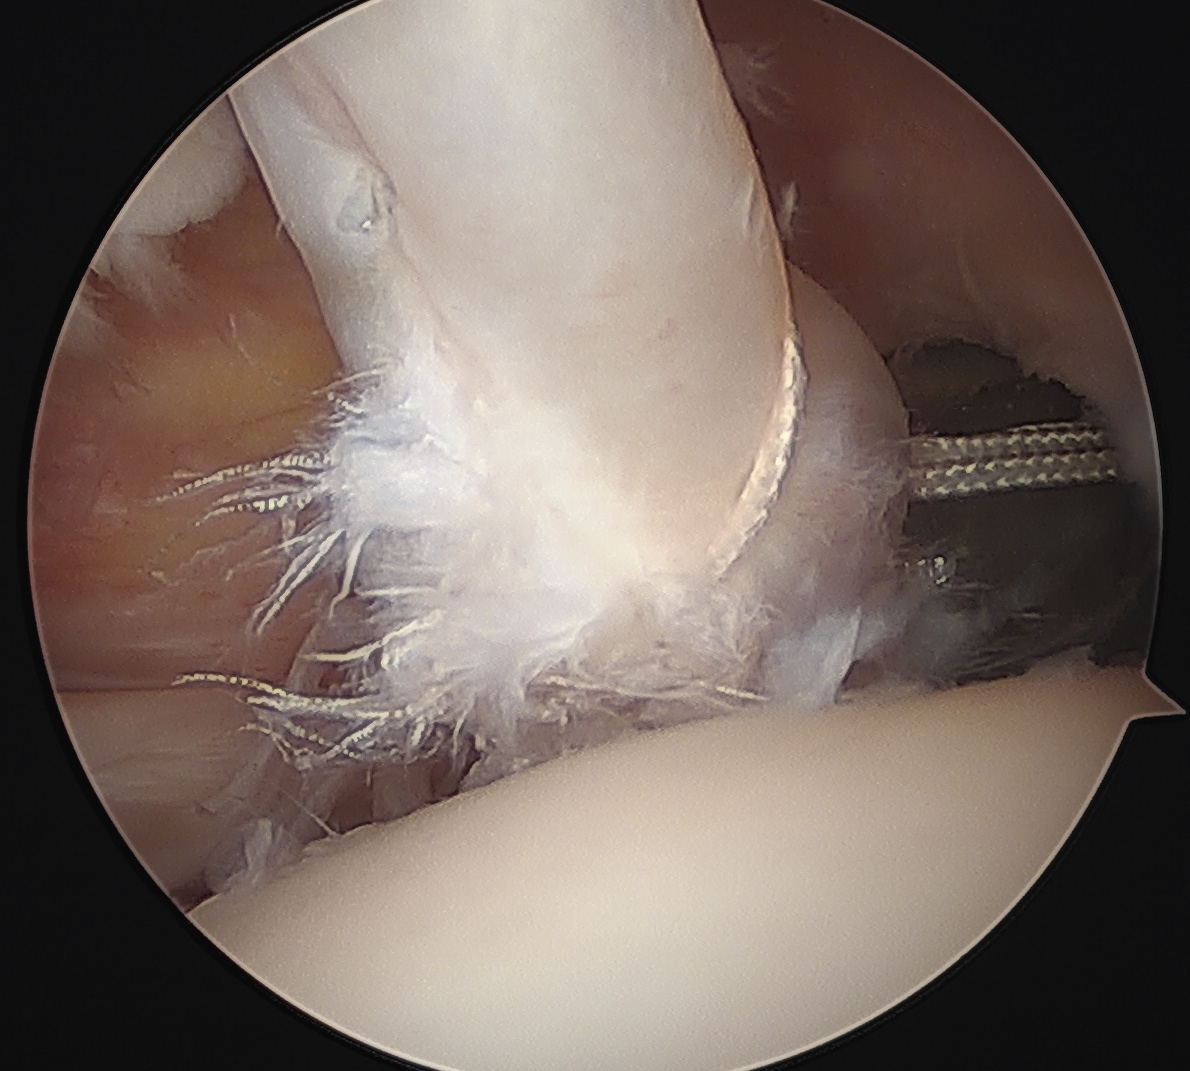

Options

Subscapularis repair + Tenodesis / Tenotomy

Subscapularis repair with LHB stabilization

Subscapularis repair + biceps tenodesis

Bicipital groove stabilization

Technique

Subscapularis repair

Biceps pulley repair (coracohumeral ligament) +/- reconstruction +/- bicipital groove deepening